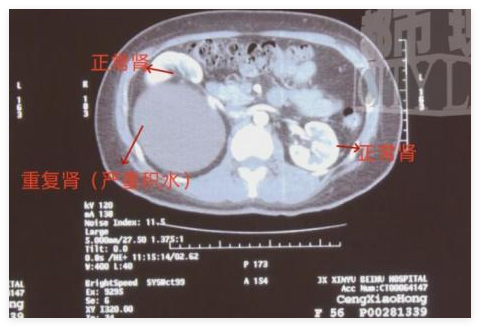

CT 檢查顯示,鄭女士的的體內(nèi)竟然有 " 三個(gè)腎 ",醫(yī)學(xué)稱之為重復(fù)腎。

新余市北湖醫(yī)院泌尿外科 主任 袁劍:右邊的腎有兩個(gè)腎,這是一個(gè)腎,這下面重度積水的又是一個(gè)腎,左邊是個(gè)正常的腎。這個(gè)積水很大,從上到下幾十層應(yīng)該有二十幾公分長,這個(gè)大小應(yīng)該是正常腎的三倍。